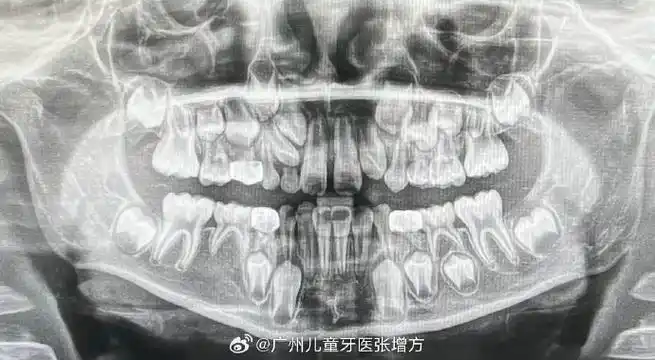

替牙期儿童拍摄全景牙片的意义